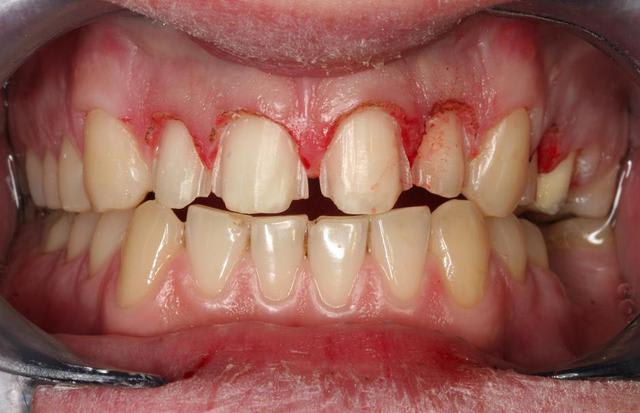

jeune homme en demande esthétique:

1 cas initial: diastème et 22 rikiki.